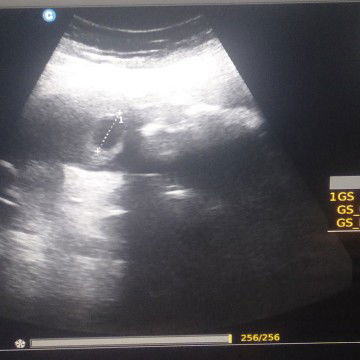

7W4D

bun kmren aku usg . . kta bidannya yg keliatn baru kantung.nya ajj . . ap dsni ad yg ngalamin sma kya aku . .